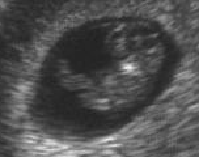

Now you are 22 weeks old, I do not have to go to the hospital anymore everyday, because your daddy is giving me the injections. Last week we saw you on the ultrasound again. You are already too big to get a nice picture for this page, but you are very beautiful. We do not know yet, if you are going to be a boy or a girl (would you like Samira?)